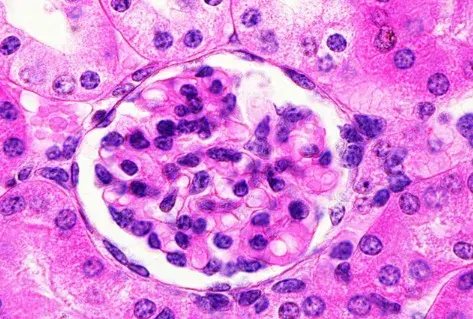

Caso clínico publicado no **[NEJM](https://www.nejm.org/doi/full/10.1056/NEJMicm2213584?query=featured_nephrology)**: Um homem de 35 anos com nefropatia por IgA procurou pronto-socorro com quadro de confusão mental, visão embaçada e convulsão há 01 dia. Duas semanas antes da apresentação ele começou a tomar ciclosporina para tratamento de nefropatia por IgA. Sua PA era de 160/80 mm Hg.

Nefropatia Membranosa: e se o paciente não responder ao tratamento inicial?

Nefropatia Membranosa: e se o paciente não responder ao tratamento inicial?

Como fazer o tratamento da Nefropatia Membranosa de forma prática!

Como fazer o tratamento da Nefropatia Membranosa de forma prática!